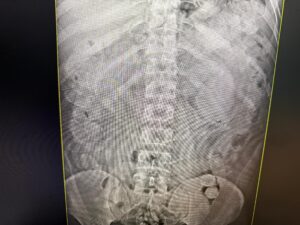

Ao apresentarem nervosismo durante a abordagem, os servidores procederam à vistoria minuciosa nas bagagens e encontraram diversas cápsulas de substância análoga à pasta base de cocaína em uma das mochilas. Após revista pessoal em um deles, mais cápsulas foram encontradas em sua cueca. Os suspeitos foram encaminhados para o pronto socorro municipal para procedimentos de verificação em raio X. Após ser indagado, um deles falou que não havia conseguido engolir as cápsulas e que as cápsulas encontradas durante a abordagem eram todas dele. Os outros três indivíduos restantes engoliram cada um cerca de 86 Cápsulas.